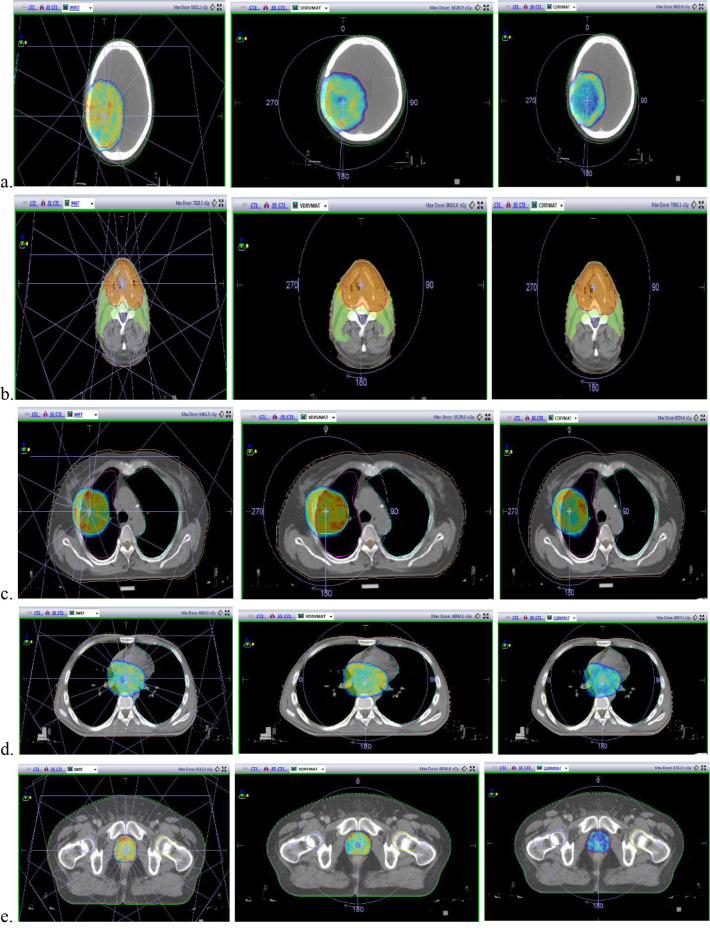

Material and methods: In this analytical study, 75 cancer patients (15 from each cancer) were selected. Step and shoot intensity-modulated radiation therapy (S&S IMRT), CDR, and VDR VMAT (variable dose rate VMAT) plans were generated for each patient using the Monte Carlo algorithm on the Monaco treatment planning system for 6 MV photon energy. For dosimetric comparison, some variables were compared, including doses to the planning target volume (PTV), OAR, homogeneity index, conformity index (CI), treatment delivery time, and monitor units.

Results: CI was higher in CDR and VDR VMAT plans compared to IMRT without any significant variation for PTV coverage V95 and PTV mean dose. In the sparing of OAR, no significant variation was found between CDR, VDR, and IMRT for the brain, head-neck, oesophagus, lung, and prostate. The treatment delivery time was reduced more, i.e., by up to 72-80% in the CDR VMAT technique compared to IMRT.

Conclusion: CDR VMAT technique generates a clinically acceptable plan in terms of PTV coverage, dose conformity, and OAR sparing as IMRT and VDR VMAT in all five cancer sites.